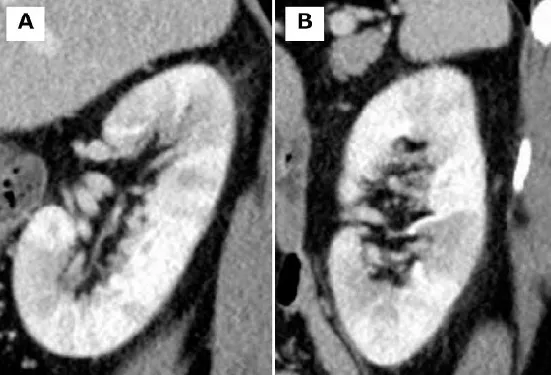

DRC indeterminada ou você esqueceu de fazer o básico? Veja tudo aqui

DRC indeterminada ou você esqueceu de fazer o básico? Veja tudo aqui

DRC “indeterminada” raramente é falta de diagnóstico — quase sempre é falta de método. Tempo de evolução, urina bem avaliada, USG renal e história clínica dirigida mudam conduta e evitam erros comuns na prática nefrológica.